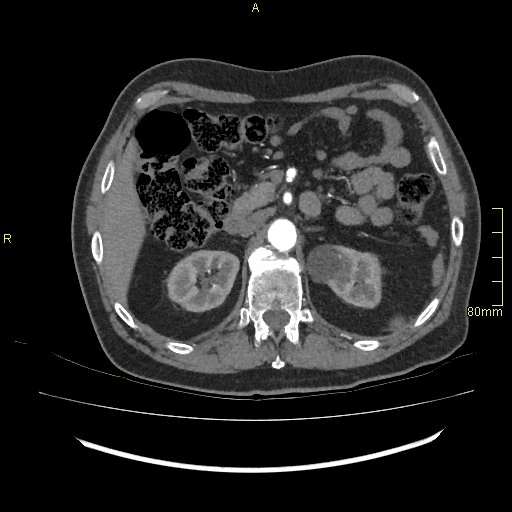

CT Angiography Lower Limb - Soft tissue window (axial)

CT Angiography Lower Limb- Soft tissue window (coronal)

CT Angiography Lower Limb- Soft tissue window (sagittal)